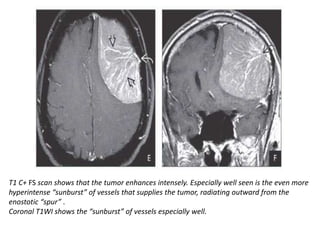

T1 C+ FS scan shows that the tumor enhances intensely. Especially well seen is the even more

hyperintense “sunburst” of vessels that supplies the tumor, radiating outward from the

enostotic “spur” .

Coronal T1WI shows the “sunburst” of vessels especially well.